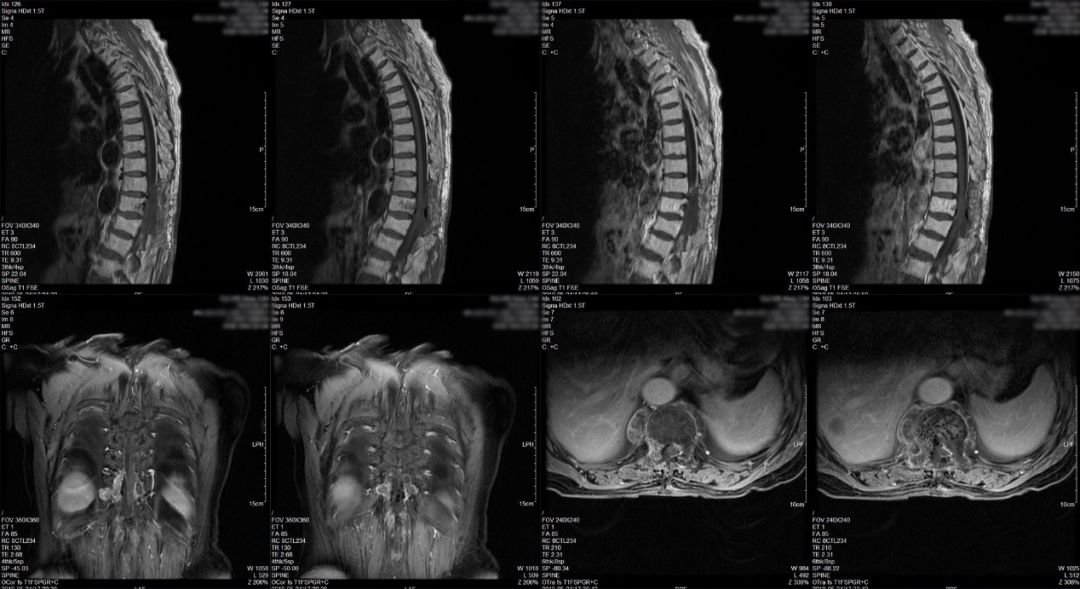

术后患者下肢无力症状较术前部分缓解,查体双下肢肌力III级(术前右下肢肌力II级),复查MRI(图3)及CT(图4)见胸10-11椎板及棘突切除后改变,胸11椎管内病变大部切除,硬膜囊及脊髓受压明显缓解。术后第6天转康复科进一步治疗,建议根据康复情况择期行放射治疗。

图3.术后第2天复查胸椎增强MRI,椎板切除,椎管内病灶大部切除,硬膜囊及脊髓受压明显缓解。